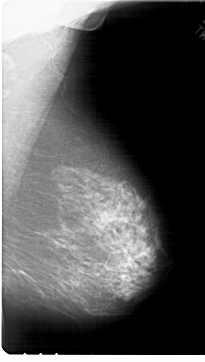

A_1789_1.LEFT_MLO

LEFT_MLO LINES 6811 PIXELS_PER_LINE 3961 BITS_PER_PIXEL 12 RESOLUTION 43.5 OVERLAY